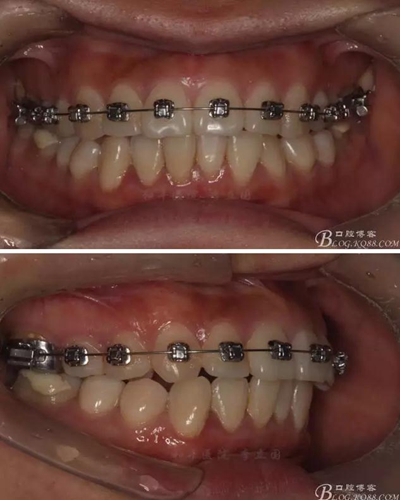

患者,女,主訴:牙齒不齊。

如圖,該病例為簡單排齊病例,但77鎖合是矯治中的關(guān)鍵所在,你會怎么處理?

該病例主要為17、27頰側(cè)位同時伴有伸長,當然種植支抗可以解決,但還有簡單實用的辦法嗎?如圖,在橫腭桿遠中延伸出牽引鉤,位置盡量遠離合平面,7粘舌側(cè)扣,牽引力的方向為壓低及舌向,下圖為兩個月的效果,17已到位,27還未到位。